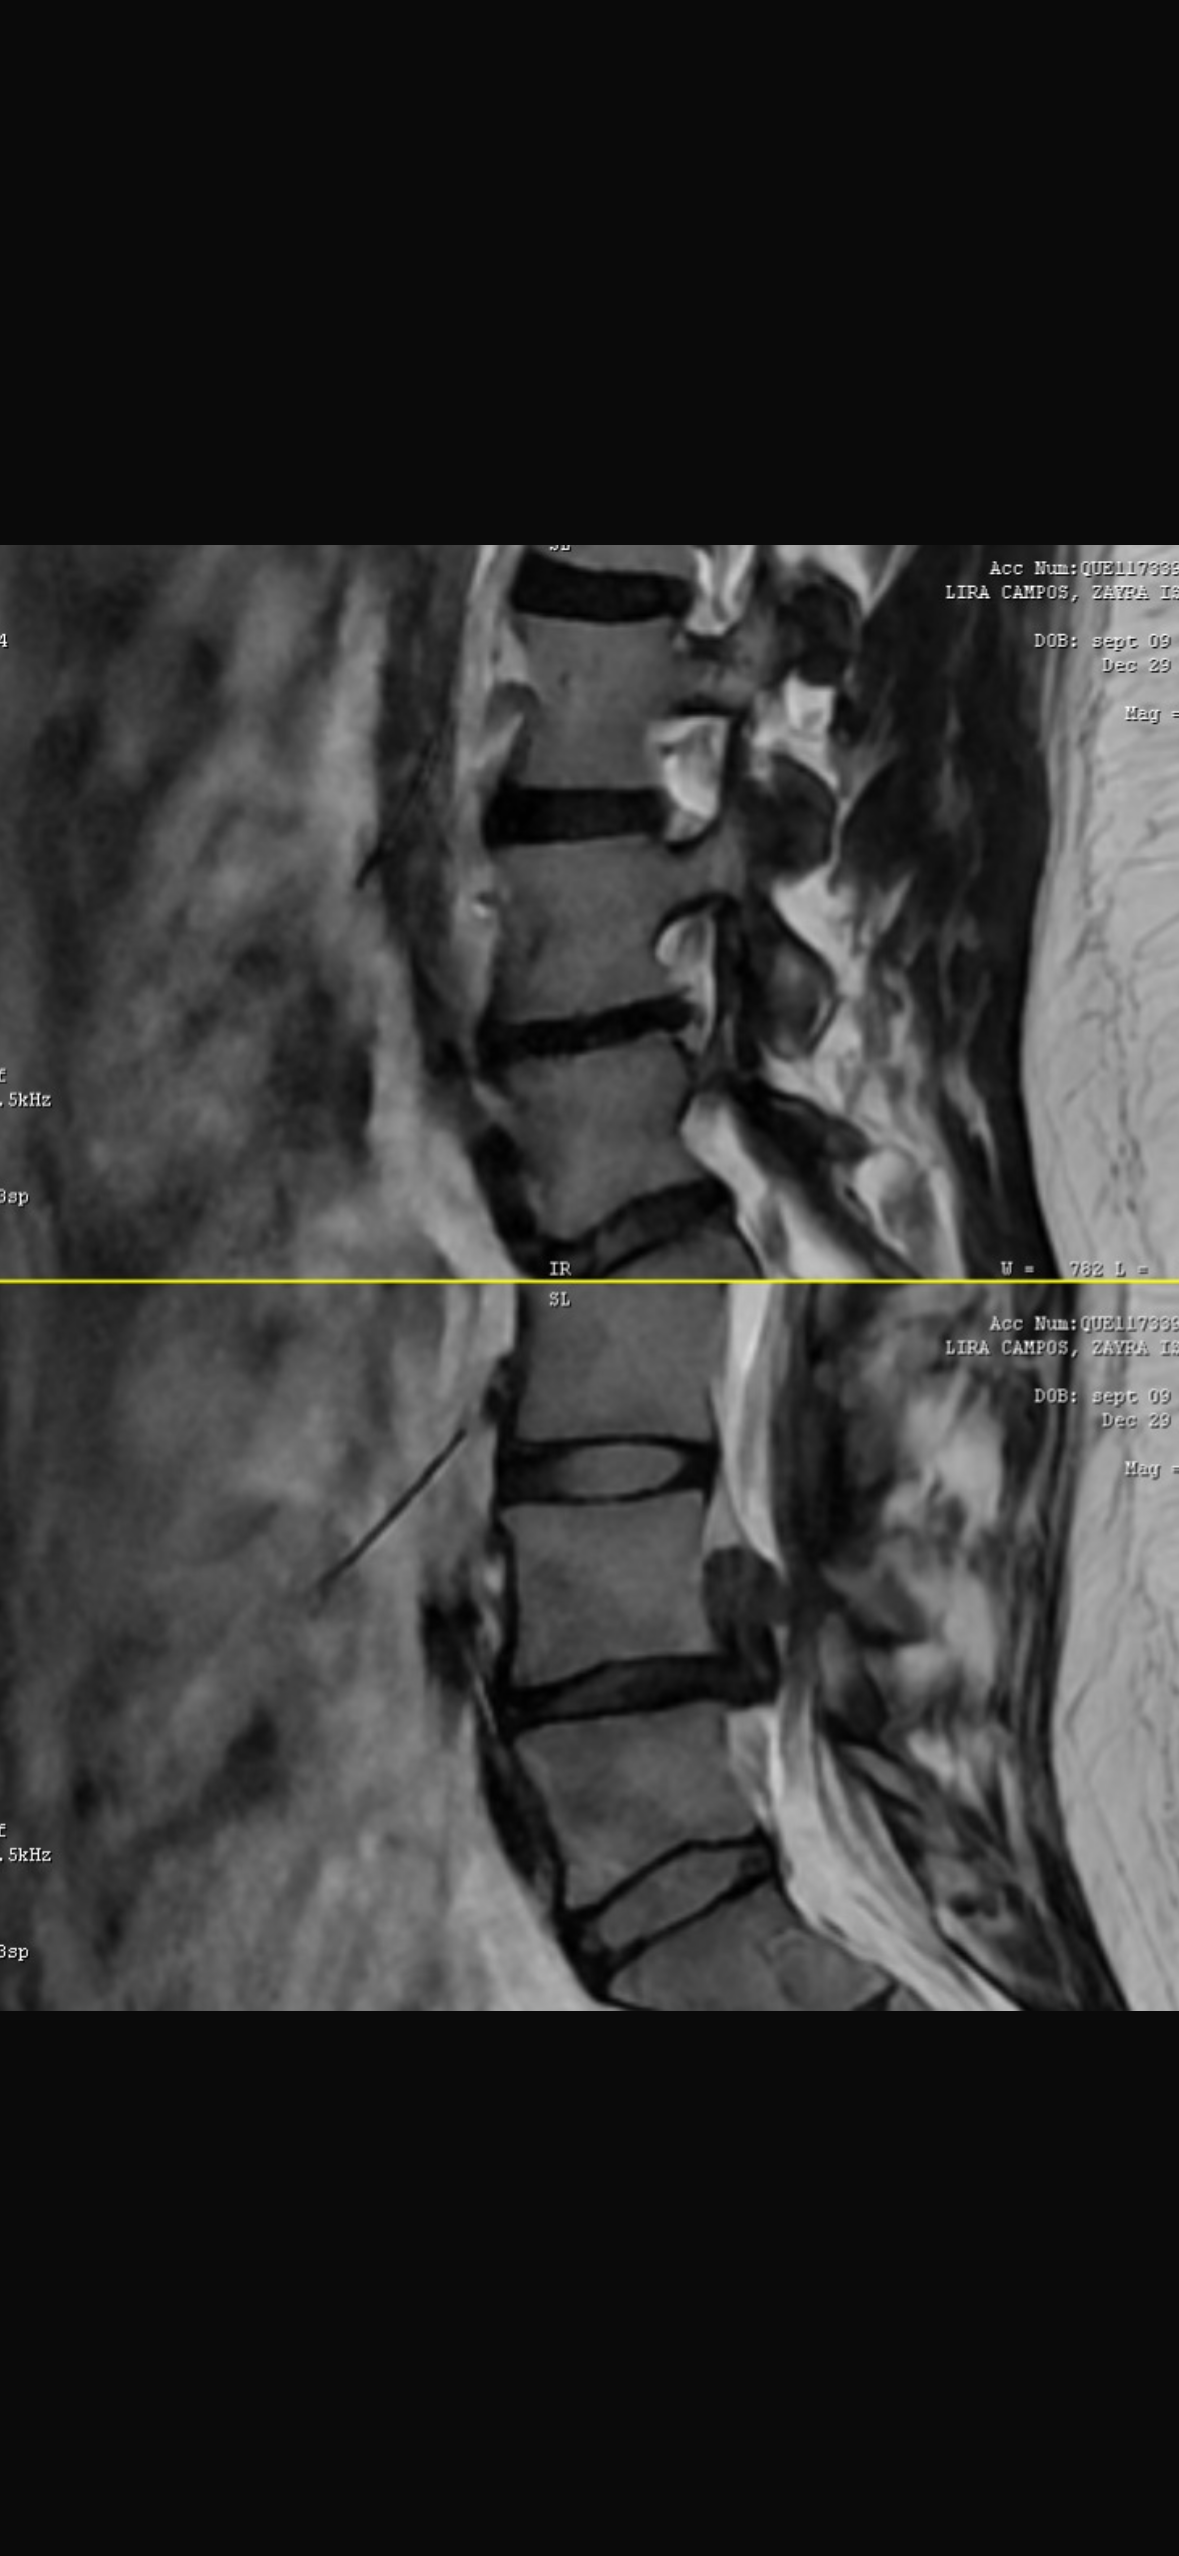

Estoy pasando por uno de los momentos más difíciles de mi vida. Tengo una hernia lumbar que está oprimiendo los nervios, lo que me provoca dolor intenso e incapacitante. El especialista me indicó que necesito cirugía urgente, ya que existe riesgo de daño permanente si no se atiende a tiempo.

He acudido en repetidas ocasiones al Hospital General, llevando resonancia y tomografía, pero no he recibido solución ni una fecha de cirugía, mientras mi dolor empeora cada día. Hay momentos en los que no puedo sentarme, caminar ni descansar, y vivir así se ha vuelto muy duro.